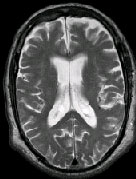

IMAGING FINDINGS: The CT was performed on AIC’s new 16-slice helical multi-slice CT (MSCT). Both routine single-slice and thin-section helical scans were obtained and 3D/Multiplanar images were performed on the Advanced 3D workstation. Fig. 1 shows an image at the level of the lateral ventricles with possible high density within the sulci on the right (arrow). To confirm this finding, an MRI with contrast was then obtained on AIC’s 1.5-Tesla high-field, short-bore Siemens MRI. Fig. 2a-b are T2-weighted images at the same level showing NO definite abnormality. T1-weighted images (not shown) were also negative. The post-contrast images (not shown) showed NO abnormal enhancement in this region, either. Diffusion-weighted images were also negative. However, Fig. 3a-b, which are FLAIR images, demonstrate clear hyperintensity within multiple sulci involving the right temporo-parietal area (arrows).

DIAGNOSIS: The FLAIR images are compatible with Subarachnoid disease. The Differential Diagnosis includes: (1) Subarachnoid Hemorrhage (SAH); (2) Meningitis; (3) Infarct; (4) Flow Artifact. Lack of enhancement is against meningitis. Acute infarct was ruled out on the basis of negative Diffusion MRI and lack of cytotoxic edema on the FLAIR images. Focal abnormality is against flow artifact (which is more diffuse and usually in the posterior fossa on FLAIR images). The clinical history of trauma and the high-density on CT and hyperintensity on FLAIR images within the sulci are diagnostic of Acute Post-traumatic Subarachnoid Hemorrhage (SAH).